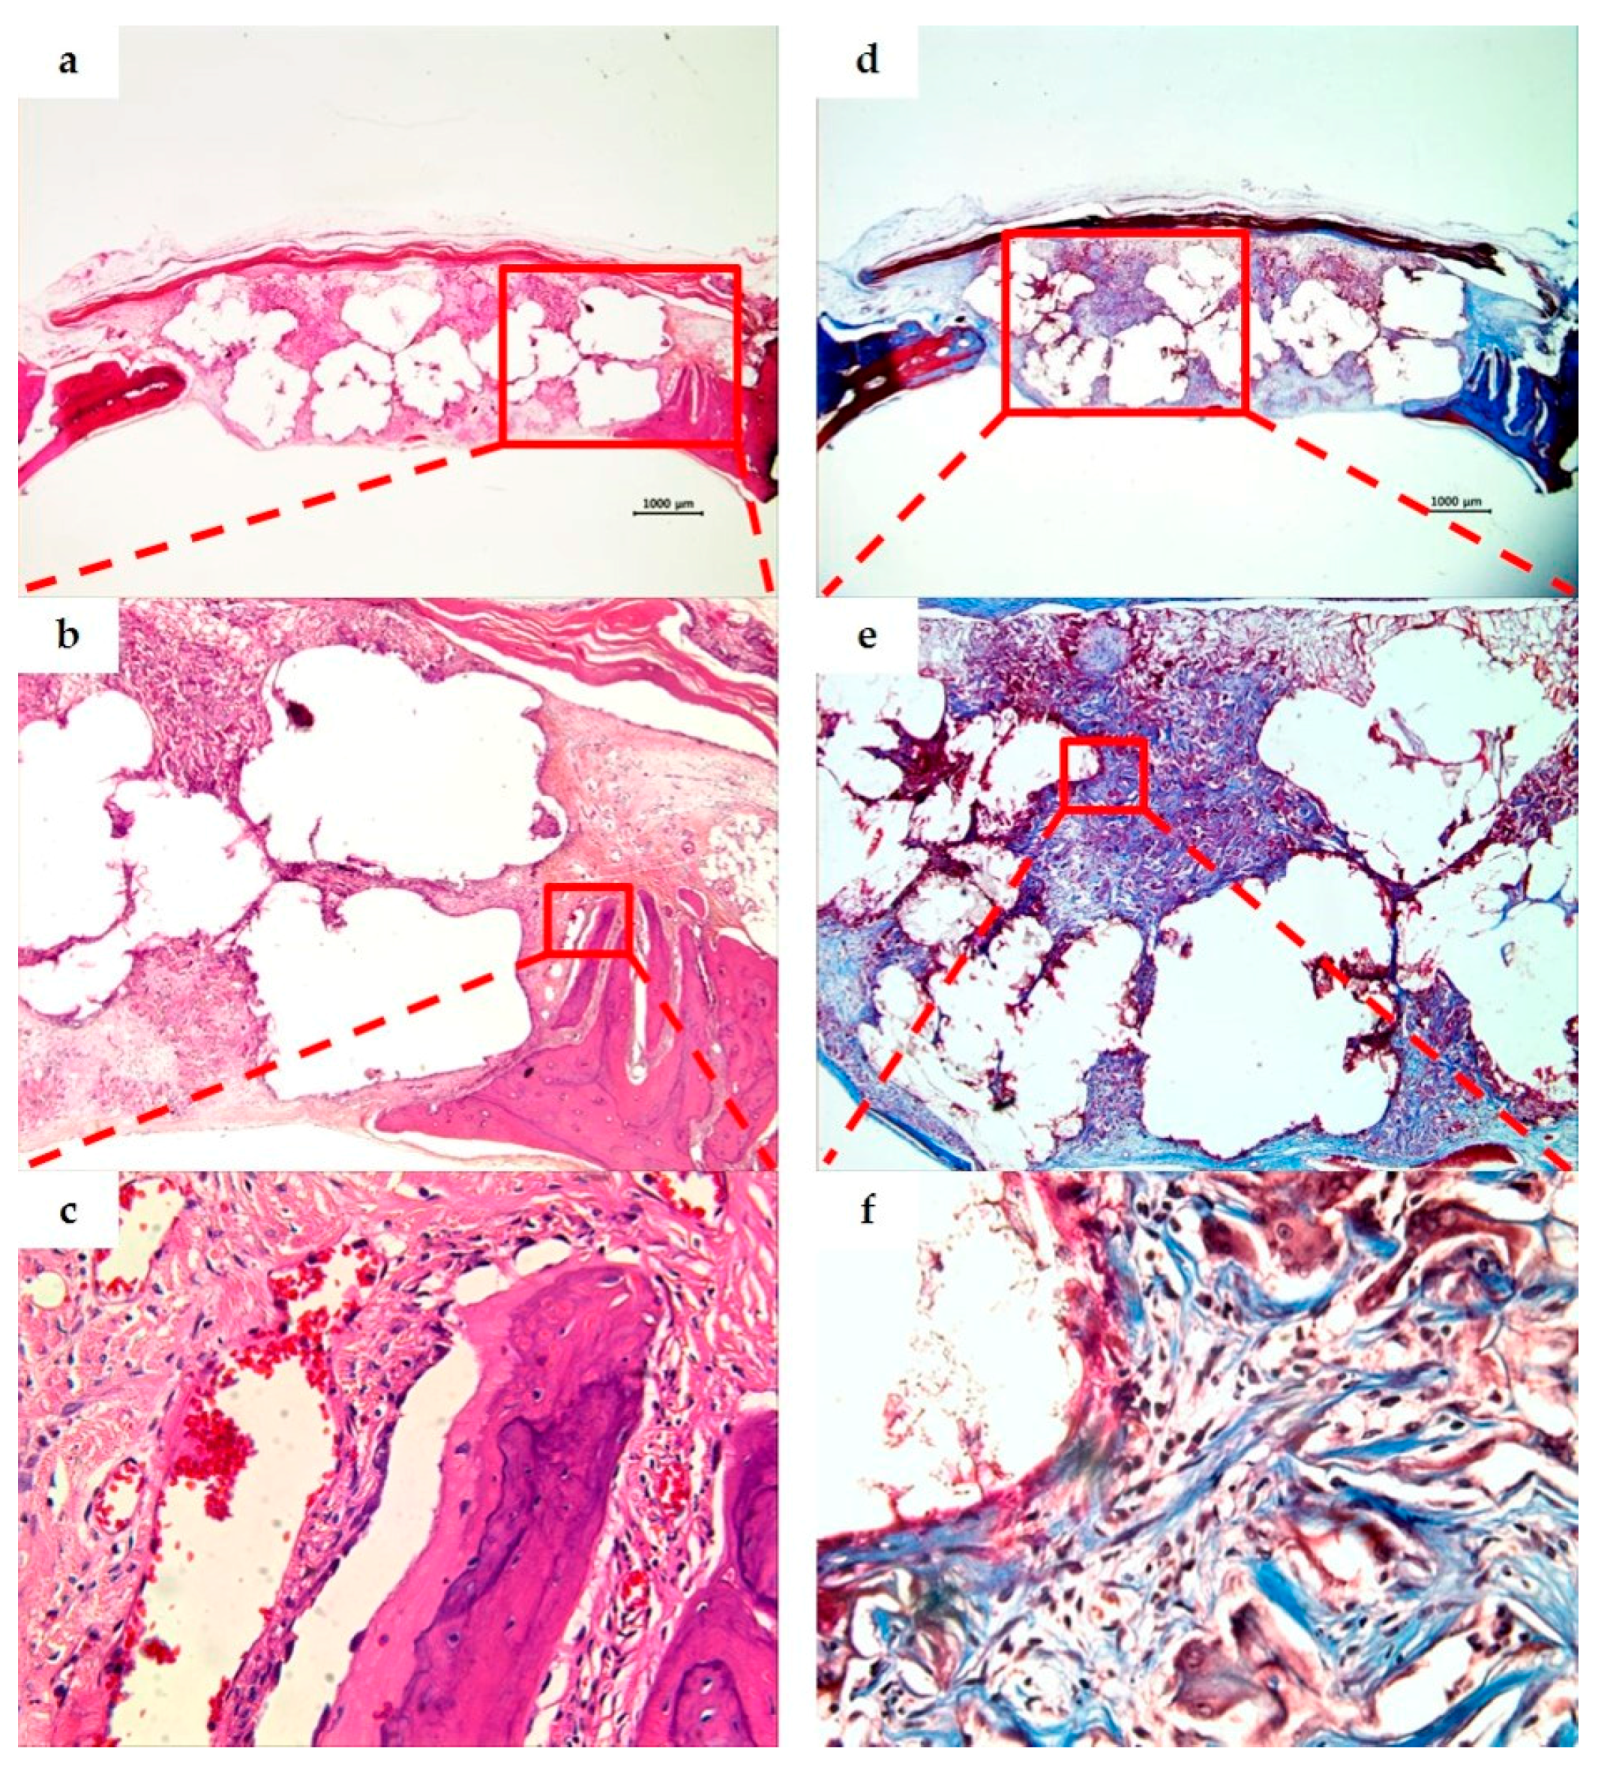

3.3. Histological Analysis